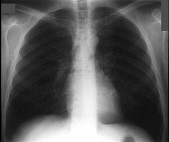

在哮喘急性发作的病程中患者出现颈部皮下气肿,胸片见图。说明此患者有下列哪一种并发症存在 ( ) HX-05051.jpg HX-05052.jpg

• A.纵隔气肿